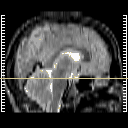

Click on sagittal image to select slice. Click on thin tickmark to change timepoint, or thick tickmark for overlay.